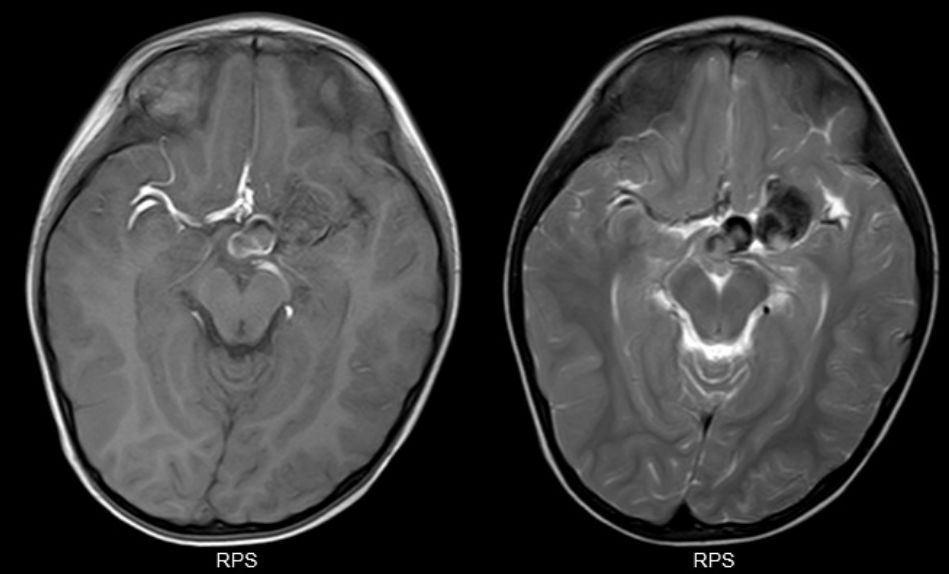

术后6月复查MR提示:动脉瘤体无明显显示,考虑血栓闭塞或瘤体自行消退缩小,周围见散在烟雾样侧枝血管(图7)。

图7. 术后6月MRA,动脉瘤体无明显显示,考虑血栓闭塞或瘤体自行消退缩小,周围见散在烟雾样侧枝血管。

术后10月复查MRA提示:瘤体及左侧A1,M1未显示伴周围侧枝血管形成,较前血管走形略清晰(图8)。

图8. 术后10月MRA,瘤体及左侧A1,M1未显示伴周围侧枝血管形成,较前血管走形略清晰。